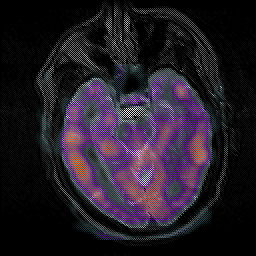

Subacute Stroke, overlay -- Slice #9

[Home][Help][Clinical] Slice 9